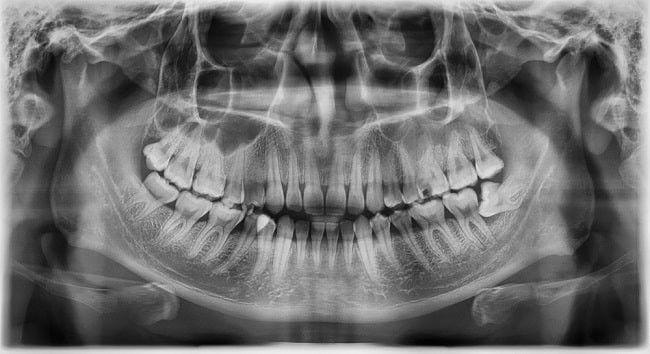

Dokter bedah mulut akan mencabut gigi bungsu melalui operasi, jika gigi impaksi. Dokter gigi akan melakukan rontgen seluruh mulut untuk melihat letak akar dan pertumbuhan gigi.

Hasil rontgen gigi miring (alomedika.com)